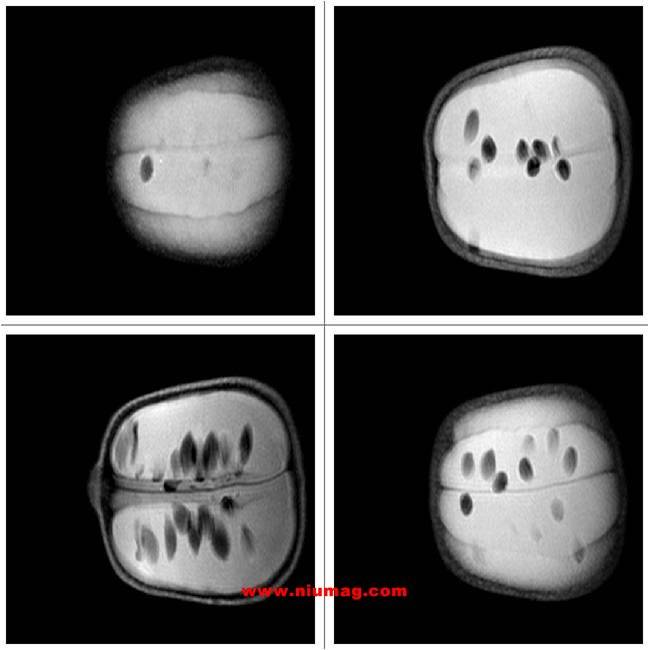

核磁共振成像水果無損檢測成像圖

玉米核磁共振多層成像圖-橫斷位

玉米核磁共振多層成像圖-失狀位